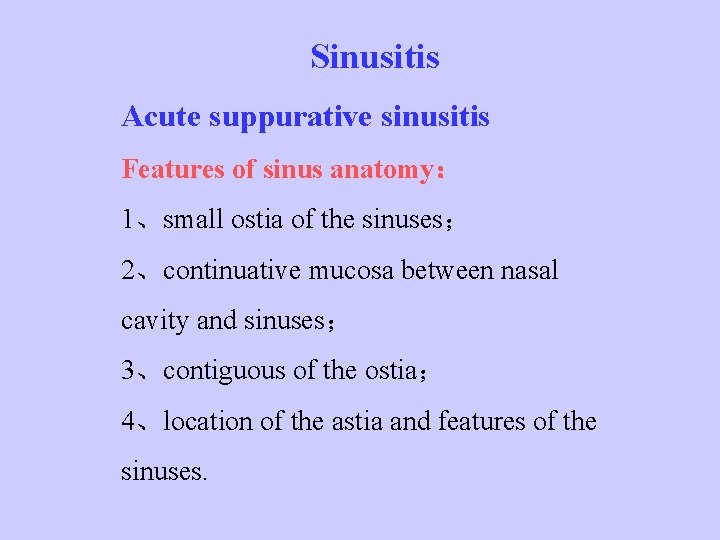

Sinusitis Acute suppurative sinusitis Features of sinus anatomy: 1、small ostia of the sinuses; 2、continuative mucosa between nasal cavity and sinuses; 3、contiguous of the ostia; 4、location of the astia and features of the sinuses.